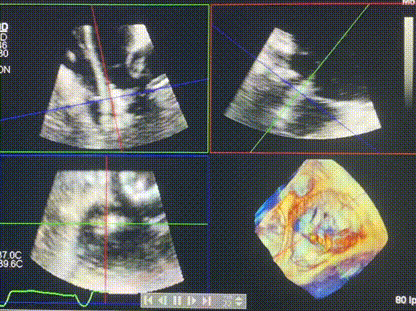

術(shù)后DSA顯示Lux-Valve Plus與Tendyne和ICD無(wú)相互影響

術(shù)后超聲顯示僅殘余微量瓣周漏

手術(shù)在全麻狀態(tài)下進(jìn)行。術(shù)者采用經(jīng)右側(cè)頸靜脈入路的方式將輸送器送入患者心臟內(nèi),在TEE及DSA引導(dǎo)下調(diào)整輸送器頭端角度,使得輸送器與三尖瓣瓣環(huán)平面垂直。在輸送器進(jìn)入右心室后釋放室間隔錨定裝置,而后釋放瓣葉夾持件(2個(gè)耳片結(jié)構(gòu))成垂直狀態(tài)。在TEE及DSA確定夾持件固定至三尖瓣葉根部且位于右室側(cè)后釋放人工瓣心房側(cè)盤片。隨后調(diào)整瓣膜同軸性以及室間隔錨定件位置(貼合室間隔),前推藏針管并固定,進(jìn)而釋放室間隔錨定裝置,并再次確認(rèn)瓣膜位置、穩(wěn)定性及同軸性,合攏輸送鞘后撤出輸送器,完成LuX-Valve Plus人工三尖瓣瓣膜的植入,僅殘余微量瓣周漏。且經(jīng)手術(shù)中心電生理團(tuán)隊(duì)評(píng)估,病人的起搏器和ICD功能沒有受到影響。